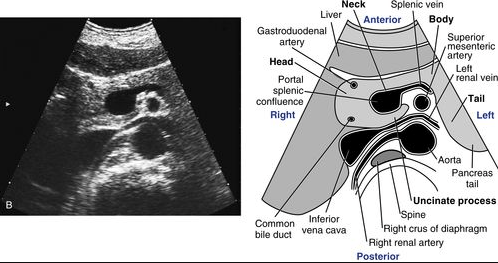

Often as we perform sonographic evaluation of the gallbladder and aorta, we pass over the pancreas and stomach, giving little consideration for the surrounding organs. In the world of anesthesiology, there has been a recent interest in using POCUS for assessing gastric contents in the perioperative period for patients taking a GLP-1 agonist for treatment of diabetes and obesity management to determine the incidence of retained gastric contents despite standard pre-operative fasting protocols.

In September 2023, the Journal of BioMed Central Emergency Medicine described a technique to utilize ultrasound to predict aspiration in patients undergoing endotracheal intubation and found a gastric craniocaudal (CC) diameter greater than or equal to 2.35 cm (Sn 88%, Sp 91%) or anteroposterior (AP) diameter greater than or equal to 5.15 cm (Sn 88%, Sp 87%) as predictive of aspiration.

The topic was also systematically reviewed by Howle et al in May 2020 in the gravid and postpartum settings, where antral cross-sectional area cutoffs were recommended in the semi-recumbent (608 mm2) and right lateral semi-recumbent (960 mm2) positions. The evidence further supports that gastric emptying is delayed by term pregnancy, labor, and during the early postpartum period.

Flynn et al. conducted a narrative review of the anatomy of the stomach and adjacent organs, exploring how ultrasound can be utilized to assess gastric content and predict the risk of pulmonary aspiration of gastric contents.

A 78-year-old woman is admitted for generalized weakness, anemia, and a week-long history of bloody stools. The hospitalist requests a diagnostic colonoscopy, and the standard bowel prep is administered orally the evening before the scheduled procedure. The CRNA, who will provide sedation, notes the patient’s long history of Type 2 diabetes, taking semaglutide and metformin. Despite being kept NPO, the CRNA is concerned about the patient’s high risk of incomplete gastric emptying. As part of the pre-anesthesia evaluation, a bedside gastric POCUS exam is performed. In the right lateral decubitus position, the measured cross-sectional area of the gastric antrum is 4.9 cm².

The CRNA recognizes that a cross-sectional area less than 10 cm2 (considered reassuring in an average-sized adult) indicates that the stomach is empty, making it safe to proceed with routine IV sedation.

A Point-of-Care Ultrasound exam is performed in the pre-op area which demonstrates:

The cross-sectional area of the gastric antrum appears to be 28 cm². Additionally, there is hyperechoic, shadowing material in the gastric antrum, making it challenging to accurately determine the posterior wall. However, the anesthesiologist interprets this as evidence of solid food in the stomach and utilizes the Perlas formula to estimate approximately 350 mL of food and liquid present.